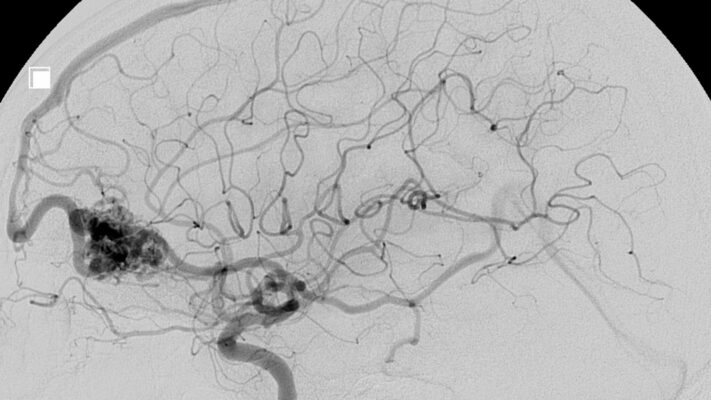

EKO (Ekokardiyografi) Nedir? EKO Nasıl Çekilir?

Ekokardiyografi, ses dalgaları kullanılarak kalbin yapısı ve fonksiyonlarının görüntülendiği non-invaziv bir tanı yöntemidir. Ultrason prensibiyle [...]